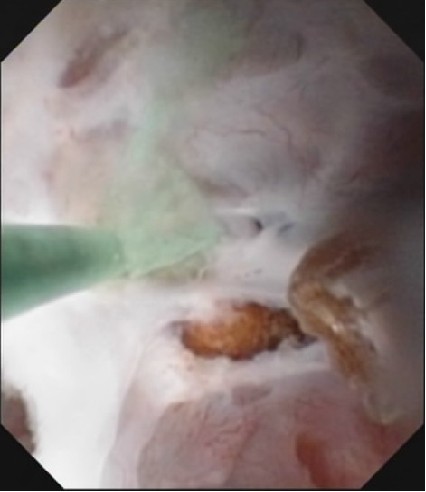

本病70%为双肾发病,每个肾脏有一至数个肾乳头受累,局限单肾单锥体罕见。由于集合管扩张、迂曲,尿液引流不畅,该处尿中成石物质浓度增高,集合管内可形成海绵肾结石,约占40%~90%,在X线检查片上可成花瓣状。双侧或单侧肾实质内多发结石,直径多为2~5mm,呈圆形、类圆形或不规则形,呈簇状、放射状、粟粒状分布或排列成扇形,位于肾锥体部是本病在平片上特征性征象。结石距肾边缘较近,一般小于1.5cm。个别结石可进入肾盂肾盏内成为游离结石。男女无明显差别,大多数患者无症状。可发生于任何年龄,2/3以上病例发生在40~60岁之间(多因合并结石和感染被发现)。

因为海绵肾结石容易反复复发,出现大结石,可行内镜取石,目前开展的输尿管软镜在治疗海绵肾结石具有得天独厚的优势,但易残留。并发感染,需要抗生素治疗。